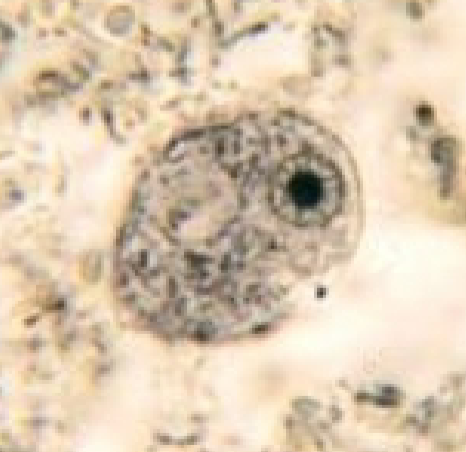

Entamoeba hartmanni (cyst)